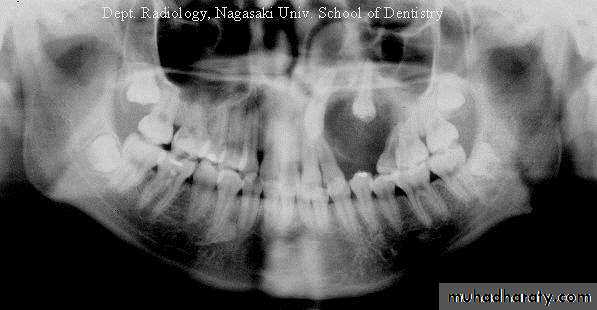

Radiographic findings

_ Well-defined expansile radiolucency

_ Root divergence, calcified flecks

_ Treatment: Enucleation, recurrence is rare